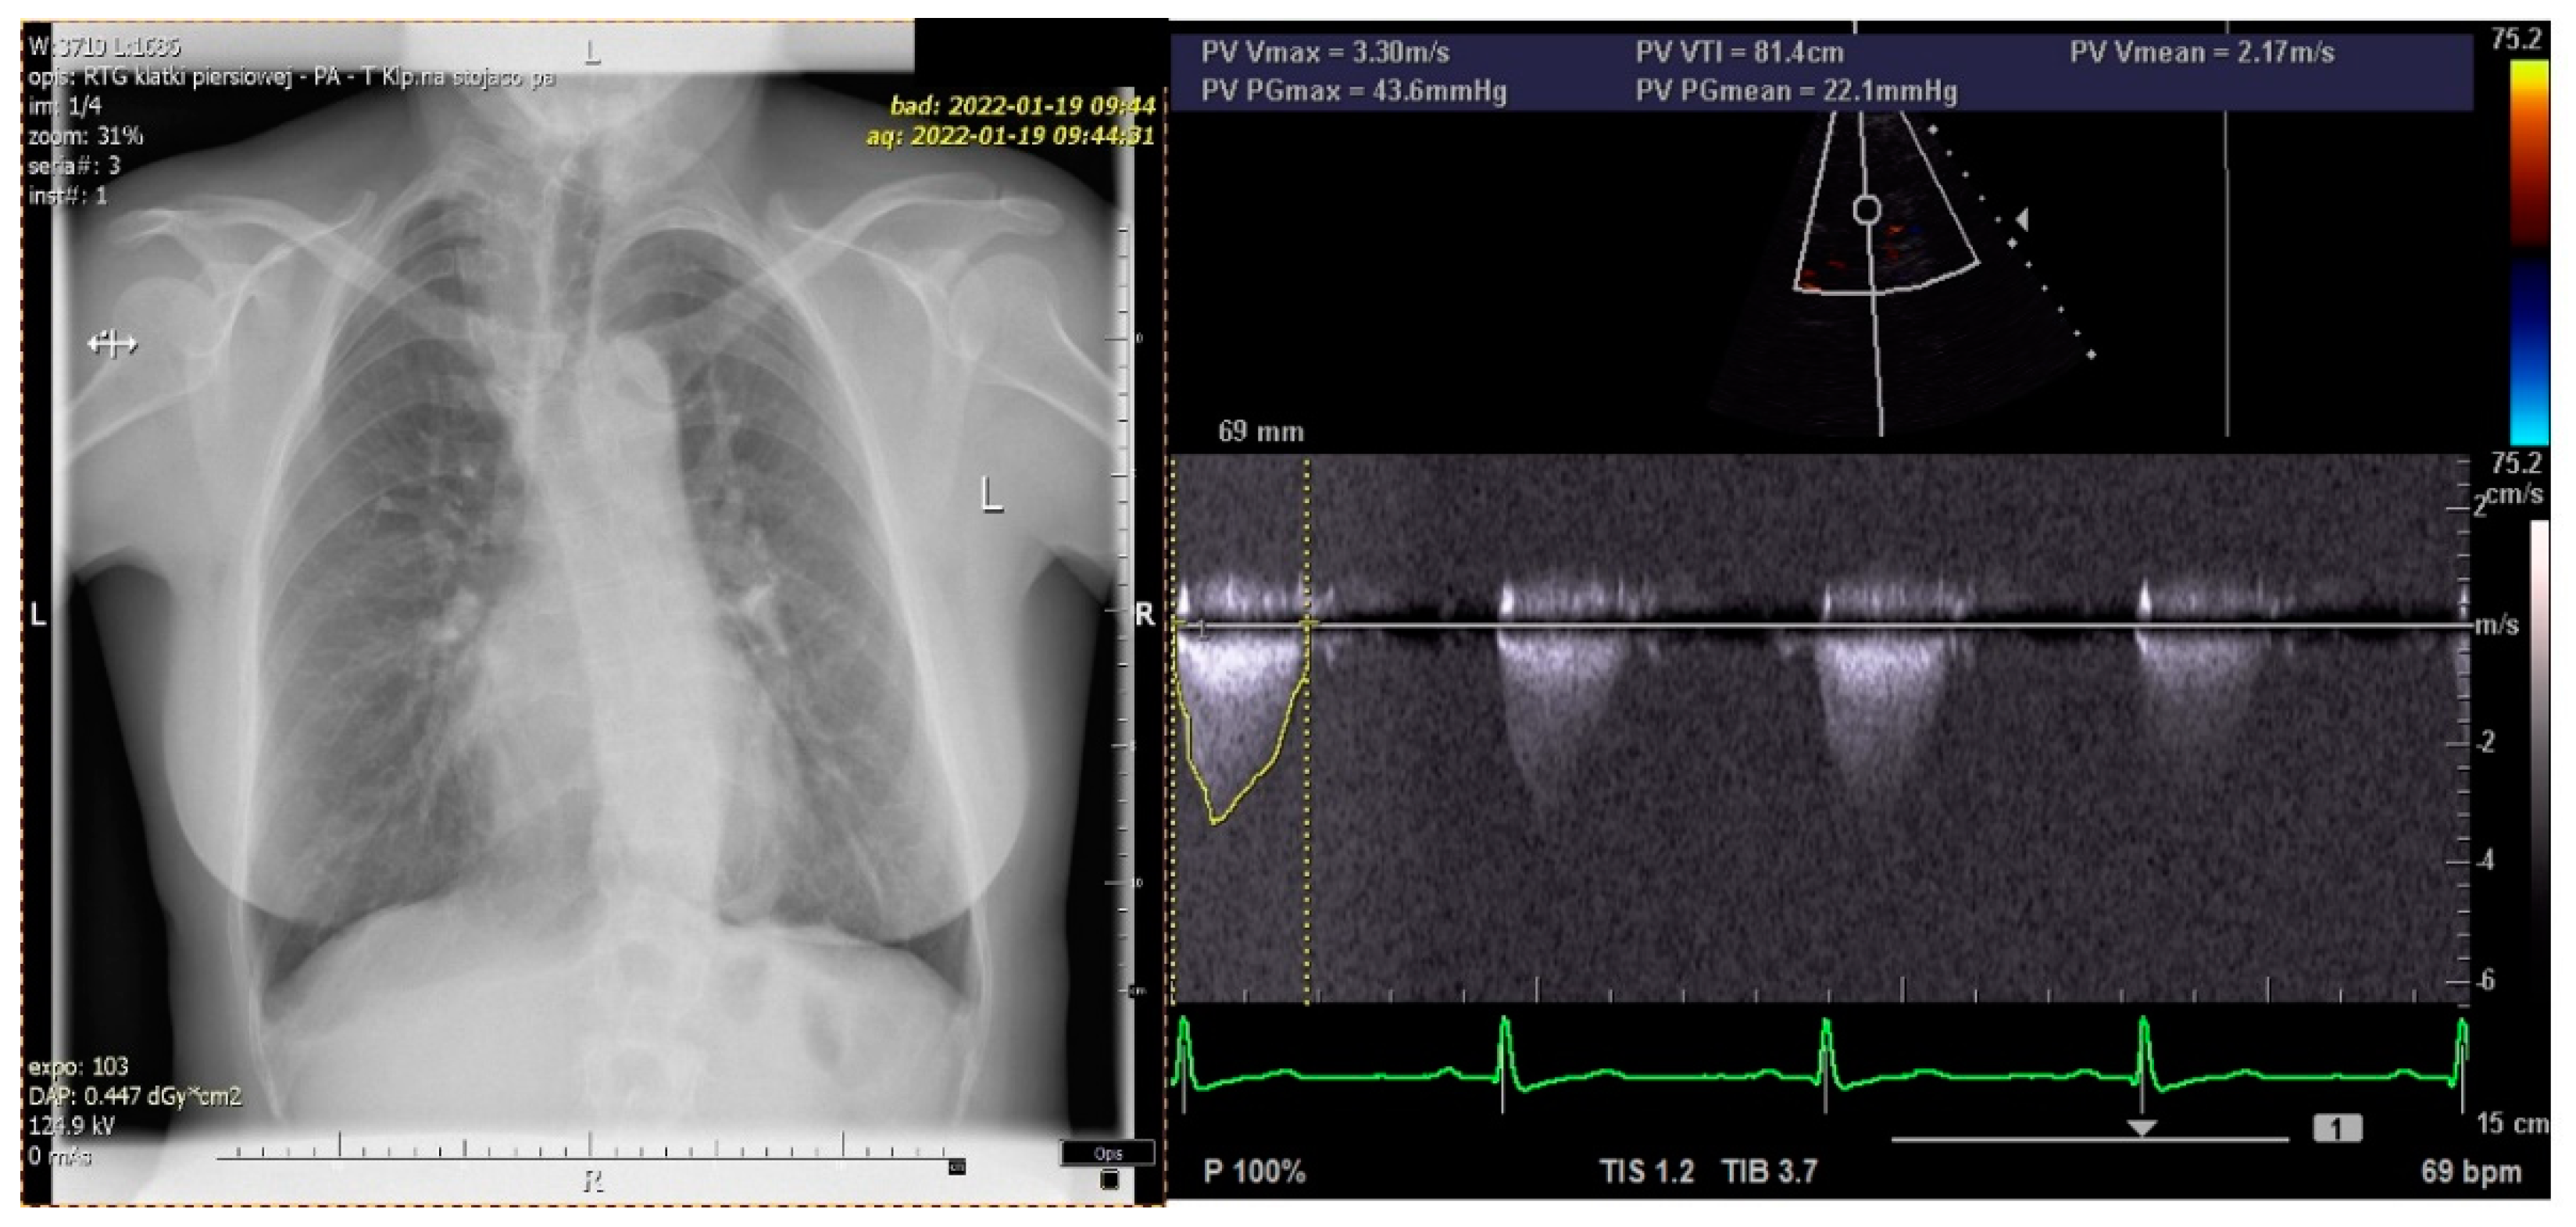

At the age of 3 years, she was hospitalized in the pediatric cardiology department due to a sudden deterioration of her general health. A chest X-ray revealed an increased blood flow through the lungs with symptoms of pulmonary hypertension and an enlarged heart, especially the right ventricle, and a wide mediastinum. A heart catheterization showed APW with a significantly increased pulmonary resistance limiting the left–right shunt through the window, an enlarged left atrium and left ventricle with a preserved systolic function. A physical examination revealed a holosystolic crescendo–decrescendo murmur with the crescendo peak closer to the first heart sound, a high amplitude, split second heart sound over the pulmonary artery (PA) and protosystolic murmur over PA and at the Erb point. The child underwent a total correction of the heart defect in extracorporeal circulation. An aortotomy was performed and the pulmonary artery was cut with a longitudinal APW closure (with a velour patch). One month after the surgery, a protomesosystolic decrescendo murmur was present in the projection of the pulmonary artery valve, apex and Erb point. In an ECHO, a paradoxical movement of the intraventricular septum was observed and the left ventricle was within the upper limit of the norm. The child was discharged from the department and followed-up with regularly. At the age of 17 years, she was hospitalized in the cardiology department for extended examinations. An ECHO examination showed a pulmonary valve regurgitation (I/II degree), PA with a widened trunk, widened ascending aorta with narrowing at the isthmus level and acceleration of flow, but without features of coarctation. The exercise tolerance test was correct, without signs of hypertrophy and damage to the heart muscle in resting ECG. A twenty-four-hour Holter monitoring also did not show any disturbances.

Figure 4). The patient’s chest X-ray reveled dilated bronchial vessels, and an ECHO examination showed an increased peak velocity of blood in the PA, indicating stenosis (at the level of the APW repair), which was stable and subclinical (

Figure 5). The patient had a healthy female child without any congenital anomalies.